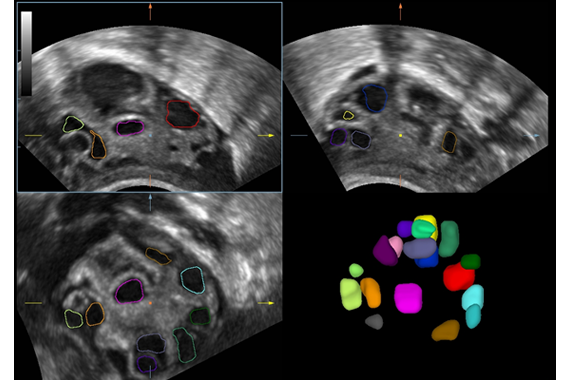

Smart FLC Smart FLC автоматически определяет количество фолликулов и рассчитывает объем каждого из них, используя данные трехмерного изображения яичника, таким образом обеспечивается точная оценка размера фолликулов, что особенно важно при ЭКО.